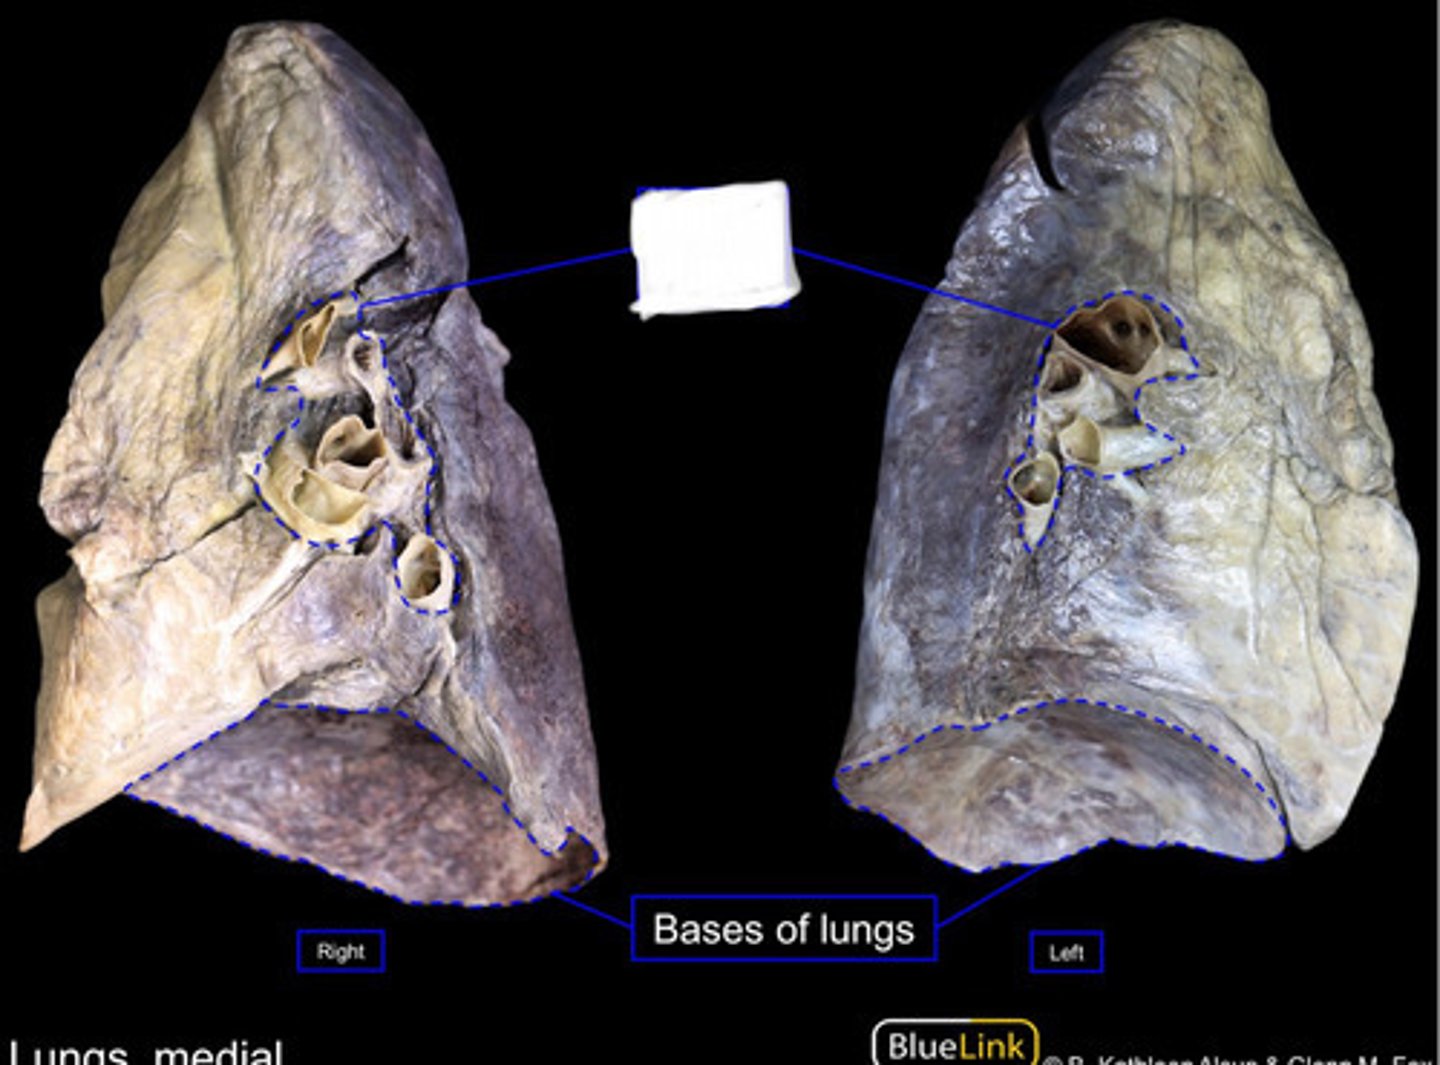

Base/Diaphragmatic Surface

Mediastinal Surface

Carina

Right Primary Bronchus

Left Primary Bronchus

Secondary Bronchus

Tertiary Bronchus

Superior lobe of right lung

Middle lobe of right lung

Inferior lobe of right lung

Superior lobe of left lung

Inferior lobe of left lung